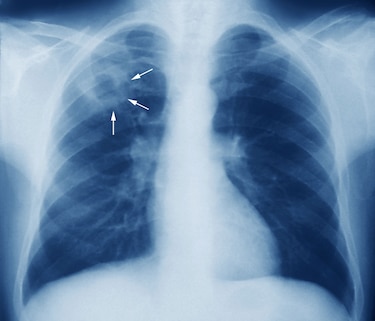

La tuberculosis es una enfermedad infecciosa que suele afectar los pulmones, causada por la bacteria Mycobacterium tuberculosis. Se transmite de una persona a otra a través de gotitas de aerosol suspendidas en el aire, que son expulsadas por personas con la enfermedad pulmonar activa, explicó Carlos Gartner, coordinador nacional del Programa de Tuberculosis de la Caja de Seguro Social (CSS).

En 2021, en Panamá se diagnosticaron mil 497 nuevos casos de tuberculosis, para una tasa de incidencia de 35 casos por cada 100 mil habitantes. Gartner indicó que las regiones de Guna Yala, Panamá metro, Panamá este, Bocas del Toro, comarca Ngäbe Buglé, Colón y San Miguelito registraron incidencias superiores a la nacional y agregó que la forma más frecuente de tuberculosis en el país es la pulmonar.

Por lo tanto, Gartner resaltó la importancia de que se realice un diagnóstico temprano. ”Cuando se tiene un cuadro de tos por más de 15 días, pudiéramos encontrar la tuberculosis cuando aún no ha hecho daño a los pulmones, la podemos tratar y evitar complicaciones”, señaló.

Pero la realidad –añadió– es que todavía se hacen muchos diagnósticos en el hospital cuando el paciente llega con complicaciones. “Un paciente que ya tiene sudoración nocturna, pérdida de peso, fiebre vespertina, posteriormente tos con sangre, en ese momento ya hay una lesión en los pulmones y ese paciente está expectorando muchos bacilos que pueden ser inhalados por cualquier otra persona sana”, subrayó.

Gartner insistió en que si se diagnostica la enfermedad en sus fases iniciales, se evitarán lesiones graves en los pulmones que luego son “irreversibles”. En ese sentido, recalcó que la tuberculosis es tratable, curable y prevenible.